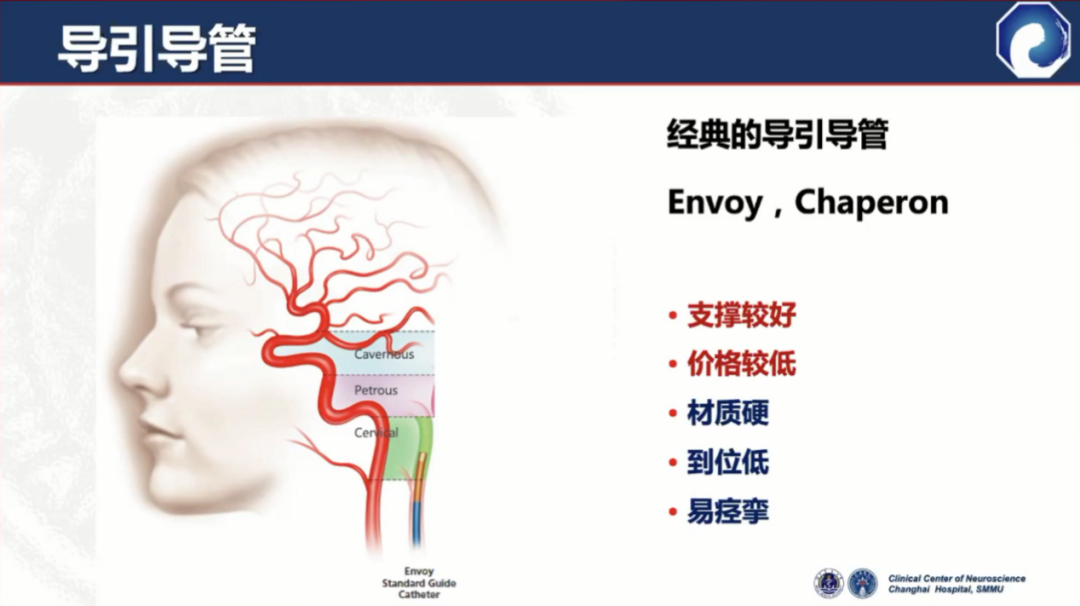

经典的导引导管:支撑性好,价格较低

材质偏硬,容易导致血管痉挛

头端到位低,不适合远端病变

在迂曲血管中通过性能较差